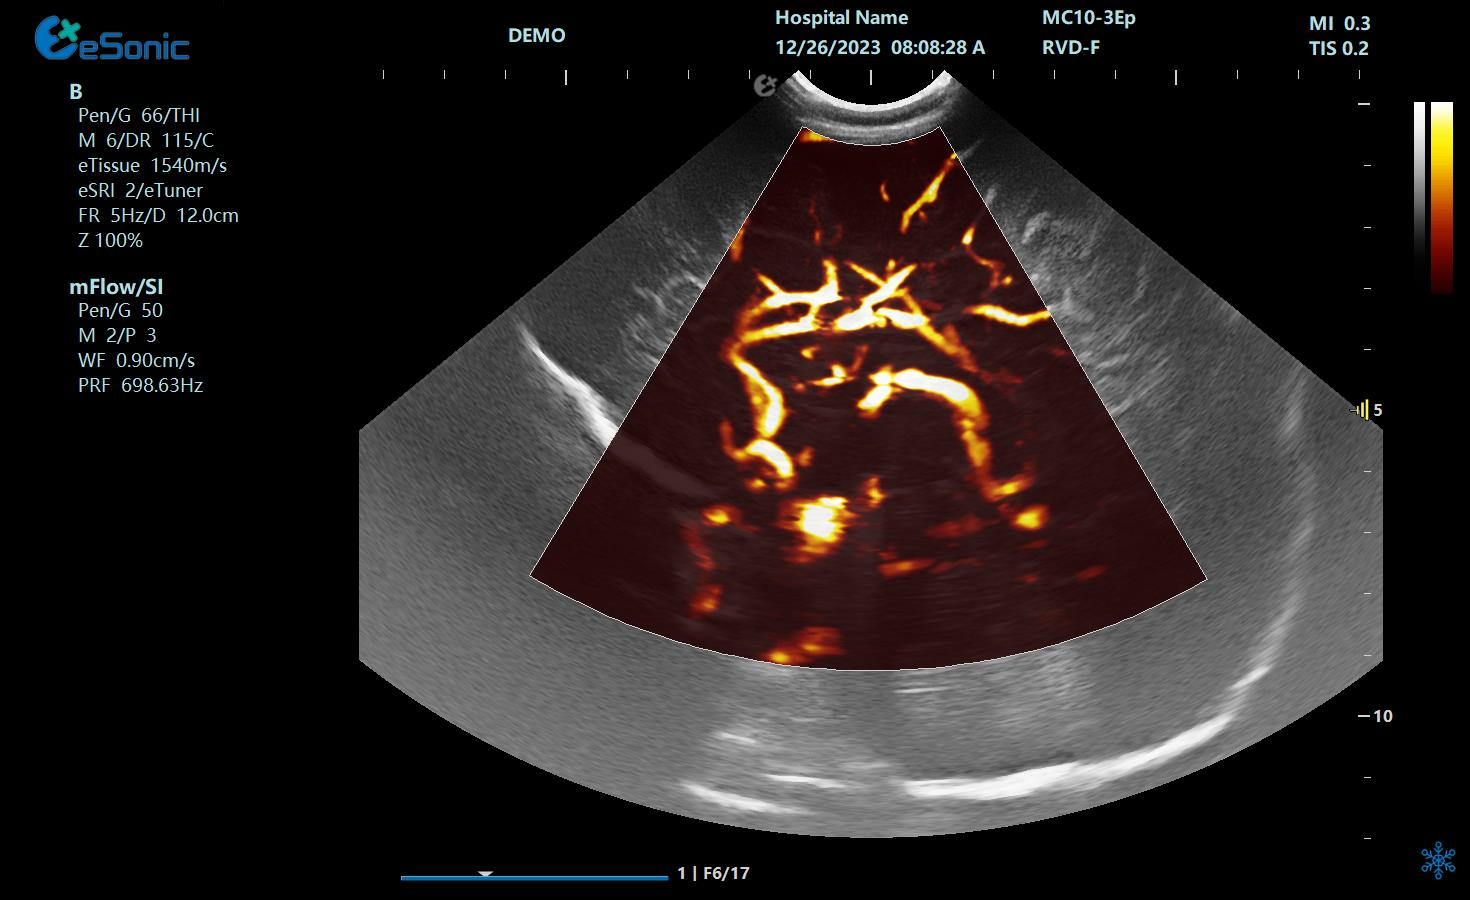

mFlow新生儿颅脑

mFlow肾移植术后评估